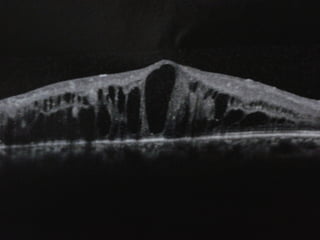

ERM – CME – CNM – ME – CSME – POST-UVEITIS – POST

INJECTIONS – MAC HOLES – PSEUDO MAC HOLES

INJECTIONS – MAC HOLES – PSEUDO MAC HOLES – PVD IN

THE X-LATERAL EYE 4 MAC HOLE PREVENTION

CME

NON CME, DIABETIC

OTHERS